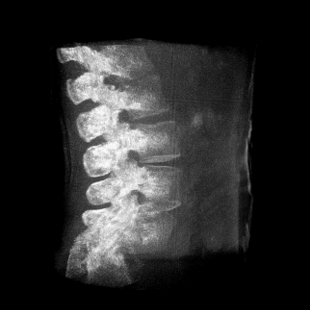

成像清晰、操作簡易、擺位便捷,主要適用于骨科、脊柱外科、矯形外科、創(chuàng)傷骨科及手術(shù)室等,能大幅度提升手術(shù)水準(zhǔn),降低手術(shù)風(fēng)險和并發(fā)癥的概率。

術(shù)中三維成像和橫斷面圖像提供多角度的手術(shù)診斷信息,輔助醫(yī)生進行術(shù)中評估判斷,諸如骨折復(fù)位情況和內(nèi)植入螺釘?shù)某叽绾臀恢?,輔助手術(shù)更好地完成。

提供更大的術(shù)中三維成像視野,采集更多圖像信息,可一次拍全全段頸椎、全段腰椎、七節(jié)胸椎、雙側(cè)骶髂關(guān)節(jié)、股骨頭及單側(cè)盆骨。